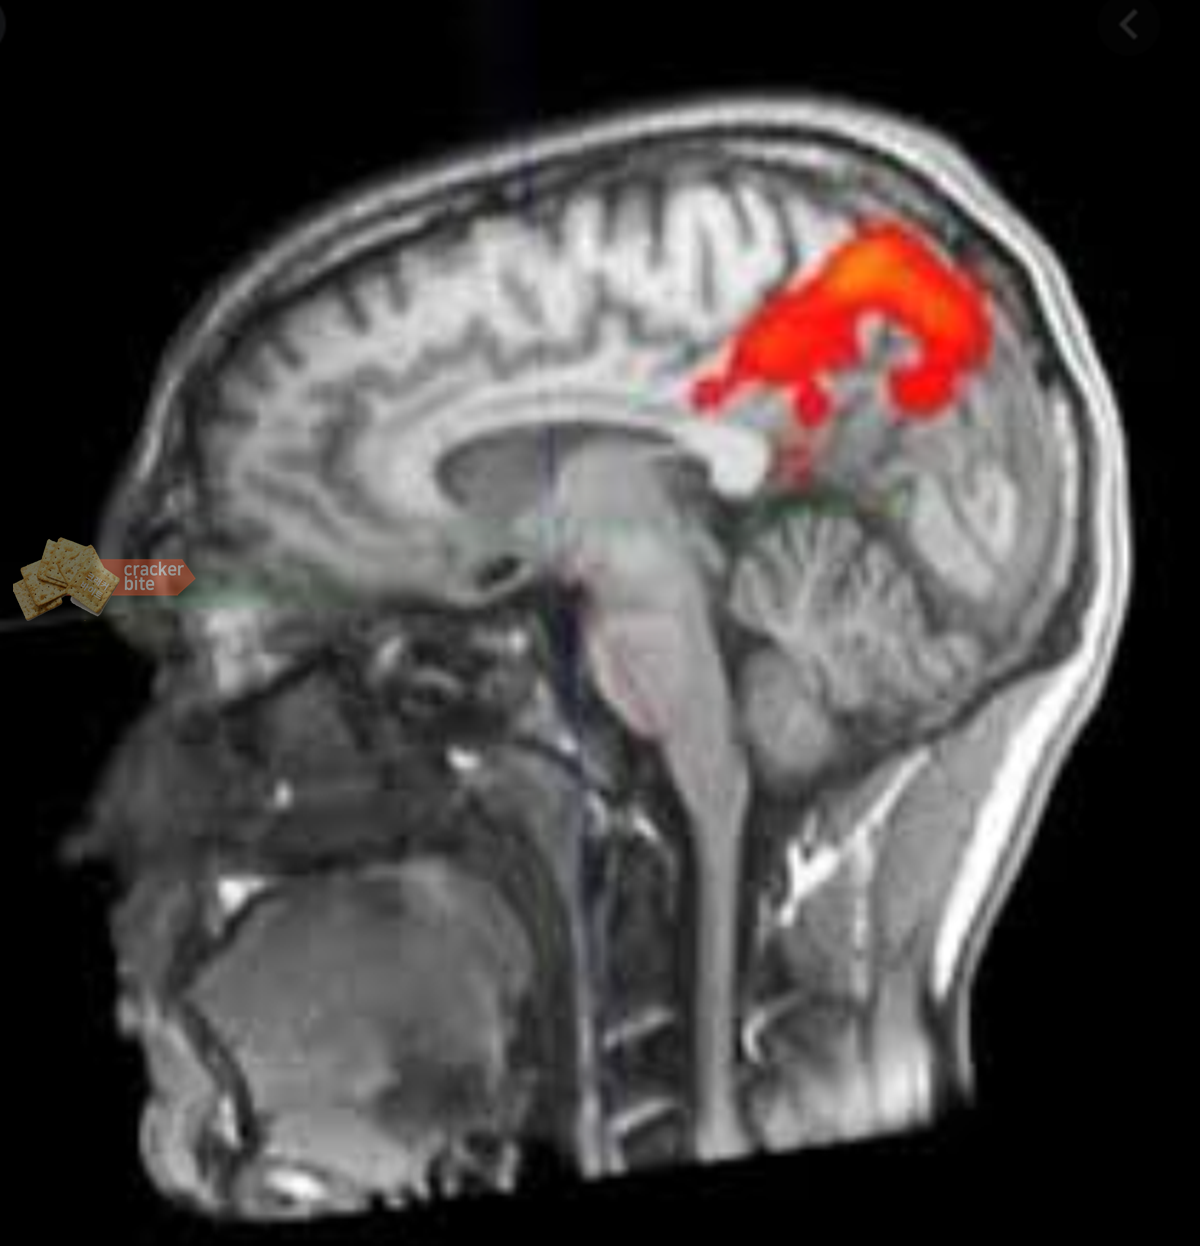

먼저 낭미충증은 갈고리촌충이라는 유충의 알을 사람이 먹게 되면서 체내에서 이 알이 부화하여 뇌, 안구, 피부 등에 자리 잡게 되는 질병입니다. 이때 뇌에 자리 잡을 경우 신경낭미충증(Neurocysticercosis)이라고 합니다.

흥미로운 건 낭미충증에 걸리더라도 여러 해에 걸쳐 증상이 거의 없을 수 있다는 점입니다. 그러다 알에서 부화한 유충이 자라게 되면서 두통이 심해지거나 위의 호주 여성 사례에서도 볼 수 있듯이 시력에도 이상이 생김을 알 수 있습니다. 방치하면 성인 뇌전증을 유발하거나 심한 경우 사망에 이를 수 있어 빠른 발견이 중요한 질병입니다.

이 낭미충증의 유충은 20년까지도 살 수 있다고 하니 제일 중요한 건 빠르게 발견하는 것입니다. 이 유충이 별다른 증상을 일으키지 않고 체내에서 죽는다 하더라도 이것이 석회화가 되어 두통이나 시력장애가 뒤늦게 나타날 수 있습니다.

낭미충증에 감염되었을 때는 보통 몇주동안 알벤다졸과 같은 구충제를 투여하여 치료하지만 뇌에 자리 잡는 신경낭미충증에 감염되었을 때는 뇌수술이 필요합니다.